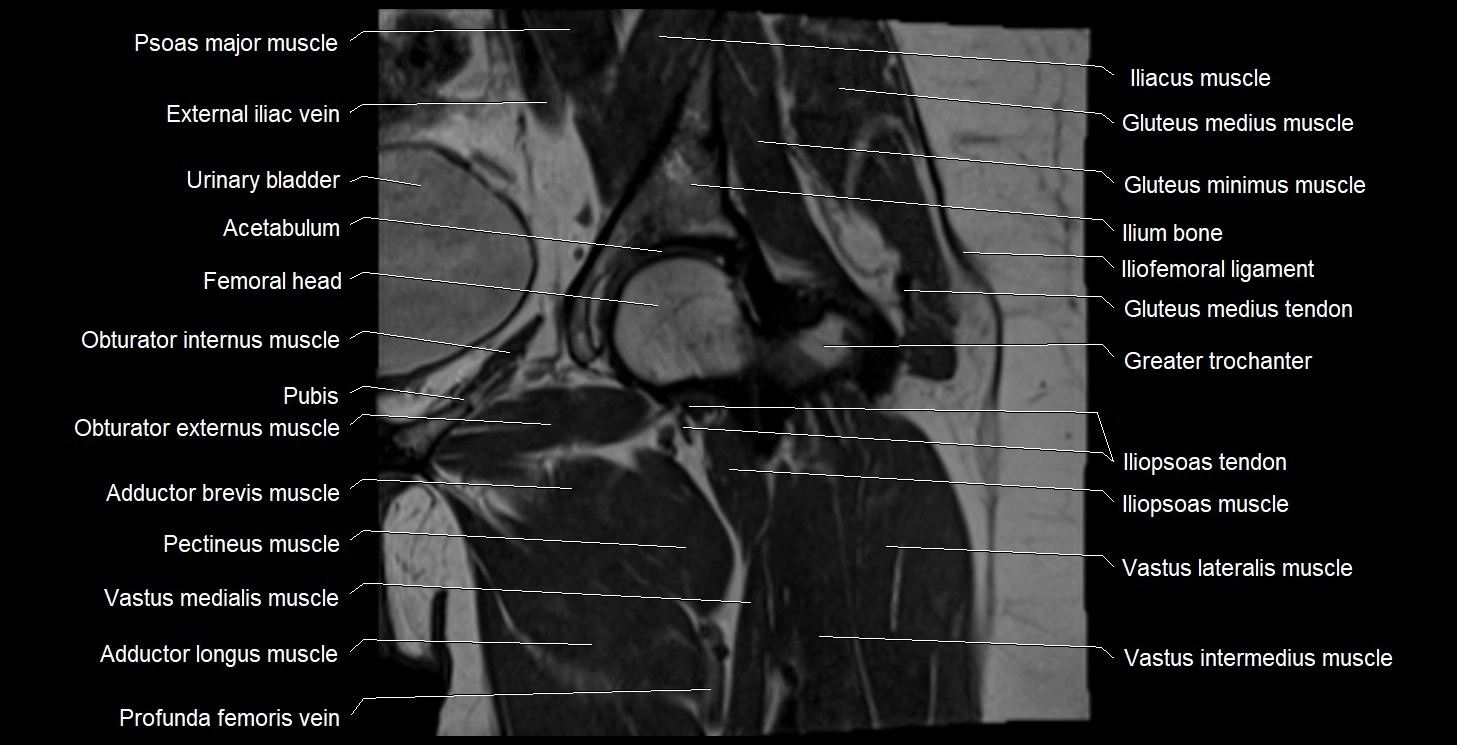

- Acetabulum

- Adductor brevis muscle

- Adductor longus muscle

- External iliac vein

- Gluteus medius muscle

- Greater trochanter

- Head of femur

- Iliofemoral ligament

- Iliopsoas muscle

- Iliopsoas tendon

- Ilium bone

- Obturator externus muscle

- Obturator internus muscle

- Pectineus muscle

- Psoas major muscle

- Urinary bladder

- Vastus intermedius muscle

- Vastus lateralis muscle

- Vastus medialis muscle